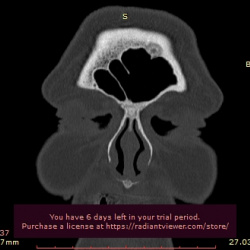

Добрый день. подскажите пожалуйста как описать верхнечелюстные пазухи... пролабирование зубов ???